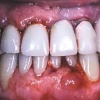

Parodontiit on mikroobide poolt põhjustatud hammast ümbritsevate kudede põletik, mille tagajärjel hävib hamba kinnituskudede süsteem ja luu, kuni hammas langeb välja.

Parodontiidile on iseloomulik igemete veritsus pika aja jooksul, tekivad igemetaskud, mis õigeagse ravi puudmisel arenevad luutaskuteks.

Põletiku tagajärjel hävib hammast ümbritsev luu ja asendub põletikulise granulatsioonikoega, mille tagajärjel hakkavad hambad liikuma ja muudavad oma asendit üksteise suhtes. See omakorda põhjustab hammaste funkstioonihäireid.